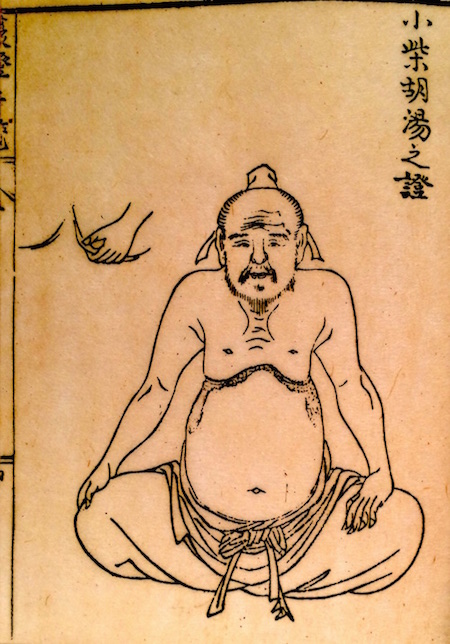

前回に続き腹證奇覧に記載されております、

小柴胡湯についてです。

小柴胡湯

胸脇苦満ノ毒、浅薄ナル者ノ圖也。

按之而知ノ傳、圖ノ如ク、

脇下肋骨ノ端ヲ指ニテカヽゲミルニ、コタユルモノアリ。

是薄キ苦満ノ毒ナリ。

又、心下ヲ按テ少シクコタユルモノナリ。

是即痞鞕ナリ。世二積聚ト号スルモノ、此ノ證多シ。